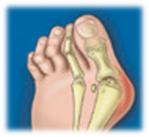

Juanete (hallux valgus)

Juanete

Un juanete es un agrandamiento de la articulación de la base del dedo gordo del pie – la articulación metatarsofalángica – que se produce al desplazarse el hueso o el tejido de la articulación del dedo gordo. Esto fuerza al dedo a doblarse hacia los otros, creando un bulto de hueso, frecuentemente doloroso, en el pie. Como esta articulación soporta gran parte del peso del cuerpo al caminar, los juanetes pueden ser extremadamente dolorosos si no se tratan. La propia articulación metatarsofalángica puede volverse rígida e irritada, haciendo difícil o imposible incluso llevar zapatos.

El tratamiento del juanete (Hallux Abductus Valgus) depende del grado de deformidad, la edad, la actividad del paciente y las manifestaciones clínicas presentes. Podría distinguirse entre tratamiento preventivo/conservador y tratamiento quirúrgico. El podólogo es el profesional sanitario especializado en el diagnóstico y tratamiento de las enfermedades de los pies, por lo que el diagnóstico certero y las opciones de tratamiento, sean conservadoras o quirúrgicas, deben ser valoradas por dicho profesional de acuerdo con las expectativas del paciente.